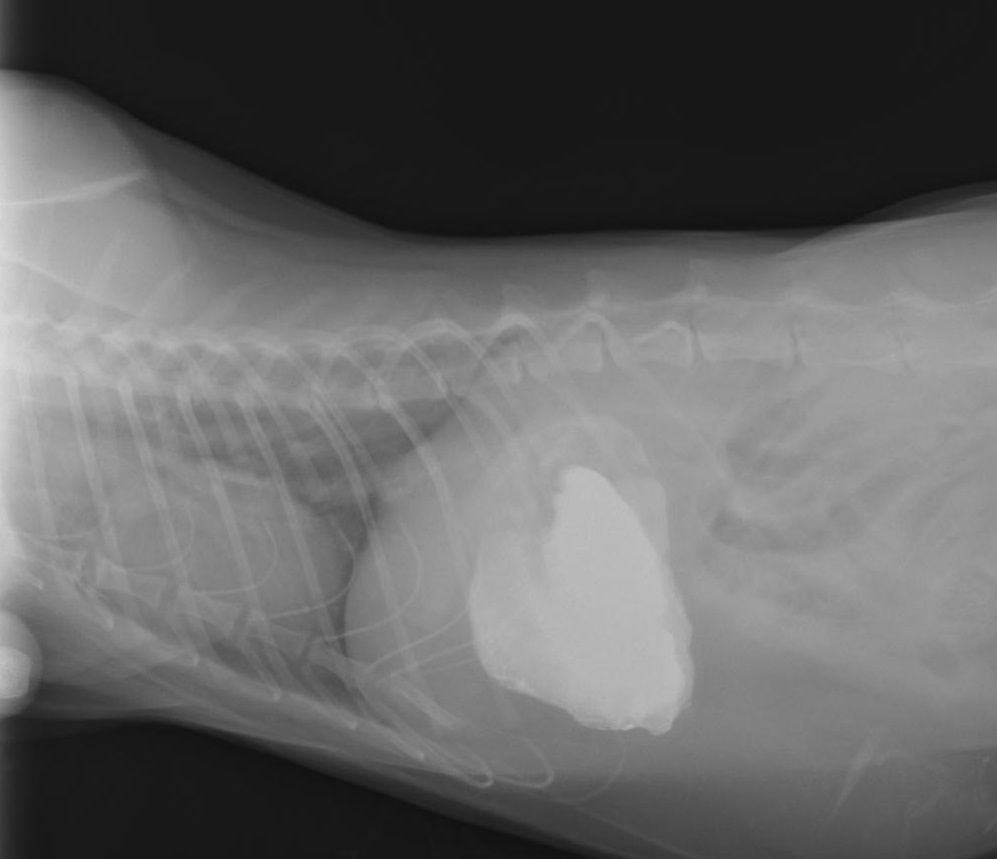

腸閉塞(ひも状異物) 松戸市・市川市 - かんじ動物病院

広島県呉市「石崎動物病院」 猫の十二指腸異物と慢性嘔吐について